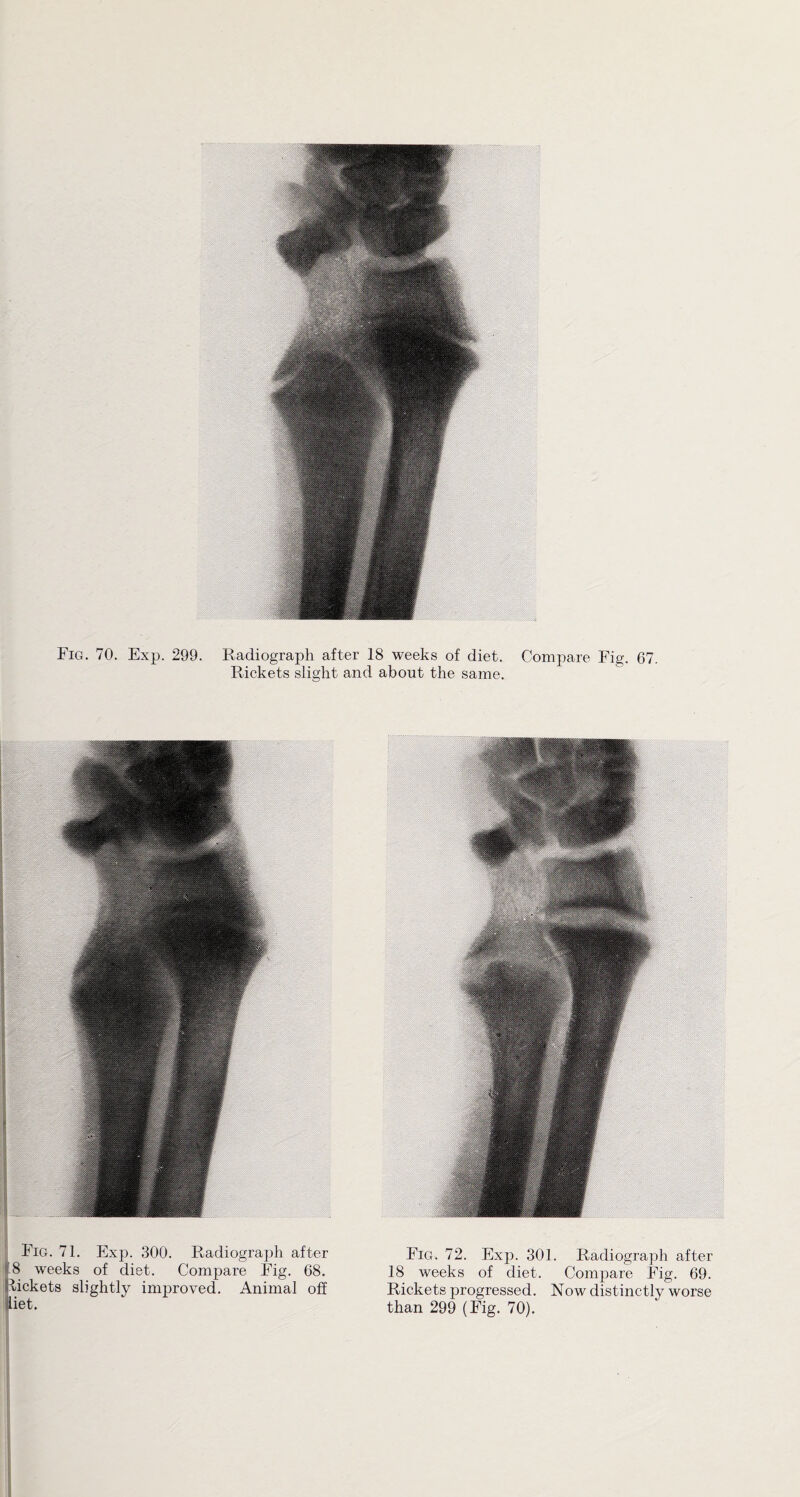

101/128 (page 101)